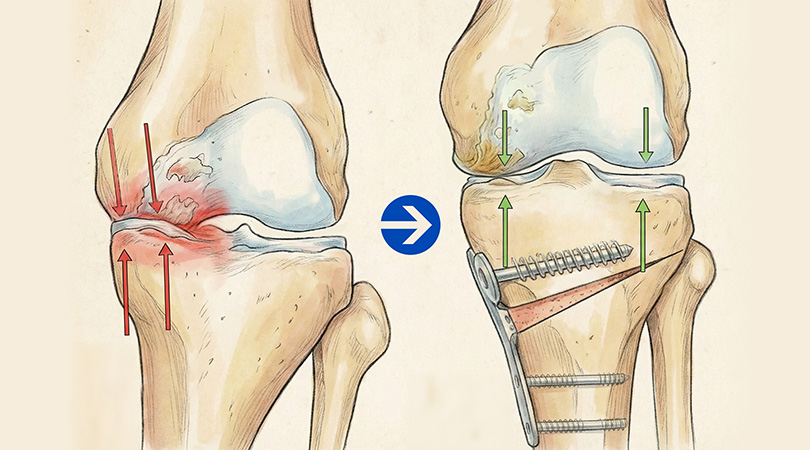

최소절개 무릎 절골술 과정

-

01

정강이뼈(경골) 윗부분을 약 3~5cm 절개한 뒤, 정강이뼈에 금을 냅니다.

02

정강이뼈 윗부분을 미세하게 벌려 인공뼈를 넣을 공간을 만들어줍니다.

03

벌려진 공간에 인공뼈를 넣어 틀어져 있던 다리 축을 정상 각도로 바로잡습니다.

04

바로잡은 각도가 잘 유지되도록 금속 플레이트와 나사로 단단히 고정합니다.

최소절개

Before

O자 휜 다리와 내측 무릎 관절염으로 무릎 안쪽 간격이 좁아져 서로 충돌하는 상태

After

체중 부하를 무릎 바깥쪽으로 이동시켜 좁아졌던 무릎 안쪽 간격이 넓어지고, 다리 모양도 일자로 교정된 상태